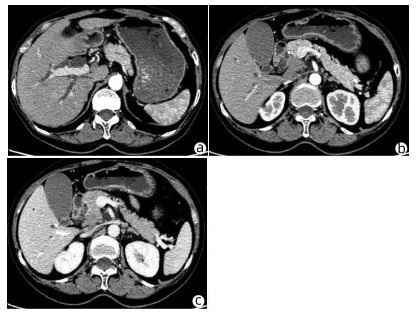

Heterotopic pancreas of the duodenum misdiagnosed as intraperitoneal tumor: A report of three cases

Xing LYU, Jianpeng ZHOU, Kai KOU, Xiaodong SUN, Guoyue LYU

2022, 38(3): 643-645. DOI: 10.3969/j.issn.1001-5256.2022.03.030

Abstract(760) HTML (351) PDF (3871KB)(58)

Abstract: